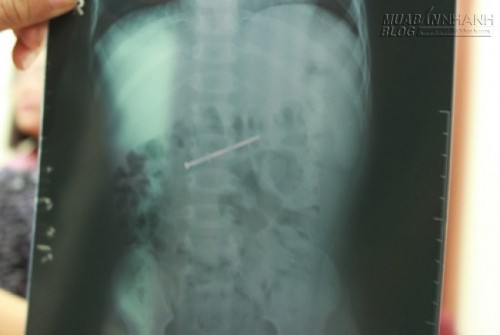

Chiều 31.10, bác sĩ Phạm Trung Dũng, Trưởng phòng nội soi Khoa Tiêu hóa Bệnh viện Nhi Đồng 1 TP.HCM cho biết, sau khi chụp phim X-quang, các bác sĩ đã phát hiện dị vật trong ruột non của bé Thành và tiến hành nội soi. Sau khi nội soi, các bác sĩ đã lấy ra được một cây đinh dài 4,5cm.

Chụp phim cho thấy dị vật trong ruột non bé Thành